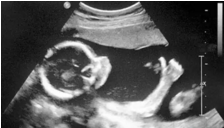

3.png

B超的原理是用超聲波穿透人體,當(dāng)聲波遇到人體組織時(shí)會(huì)產(chǎn)生反射波,通過計(jì)算反射波成像。就像挑西瓜一樣,邊敲邊看顯示病灶情況。